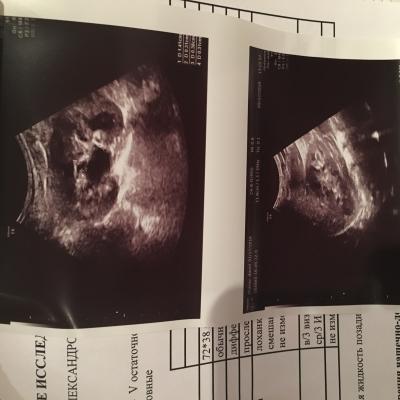

при рождении и в 3 месяца почки были без изменений.В 1 год 1 месяц после ОРВИ у ребенка появился запах ацетона в моче, в бак.посебе протеус мирабилюс 10*6 степени, лейкоциты в оам-30,УЗИ-левая лоханка 5 мм,все остальные показатели в норме,пропили антибиотик зиннат, далее фурагин,канефрон,согласно рекомендациям нефролога. Контроль УЗИ после лечения-норма,оам-идеальный.В 2 года узи -левая лоханка 8 мм,правая 8, чашечки не уанличены,остальные показатели в норме.В 3 года узи: лоханки левая 5 мм,правая 4 мм,все остальные показатели в норме,оам-норма.В 3.10 мес(ноябрь 17г)ребенку поставлен диагноз-нейрогенный мочевой пузырь(узи,урофлоуметрия),оксалурия( в Ноябре 17г. (до этого в октябре 17г. перенес орви с темп.40),Темп 38.5 без признаков орви,мутная моча,частое мочеиспускание малыми порциями,осадок в горшке кирпичного цвета, по оам все показатель в норме, кроме солей(ураты,оксалаты)в большом кол-е). Согласно результатам узи левая лоханка 22 мм,остальные показатели в норме.Лечились у нефролога,поэтапно принимали препараты для почек(фурагин,канефрон,трава пол-пола,донат магния,мин.вода фьюджи,витамин в6,веторон), для кишечника(эубикор крошка,кидз саше,лактофильтрум), диета 5 и питьевой режим 1.6 л в день,сахар по глюкометру 4.7.Вели дневник Мочеиспусканий в теч.4 дней,в среднем обьем выпитой жидкости составлял 1,5, обьем вырущенной 1.4.,мочился больше 12 раз в день.Мочеиспускание без затруднений. После лечения сделали узи,члс была в преднлах нормы, но диагностирован нейрогенный мочевой пузырь( пописал 250 мл, осталось 10 мл).анализы мочи -не придраться. Придерживаемся диеты 5 с февраля 18 г по сей день,выпиваем воды 1.6 л в день.22 августа прошли диспансеризацию и сделали для контроля узи почек/ доплер на высокочувствительном аппарате, результаты обследования меня мягко сказать огорошили- по узи чашечки расширены слева 5 мм(прежде расширений чашечек никогда не диагностировалось),лоханки слева 11 мм ,плюс в почках обнаружен песок, остальные показатели в норме,доплер-сосуды в норме.ОАМ-норма.Получается во время приема мочегонных препаратов, лоханки в норме(за исключением нейрогенного мочевого пузыря он имеет место быть),как только перестаем лечиться образуются соли .. хотя сидим на диете и пьем много воды. 4 сентября в ницрр сделали динамическую сцинтиграфию с микционной пробой, по результатам обследования функция почек не нарушена,но,слевой стороны обнаружен незначительный лоханочно-чашечный рефлюкс( результаты обследования, узи и пр.прилагаю).Какие наши дальнейшие действия? Складывается такое впечатление,что все это время мы бечили следствие заболевания,а не саму причину.. Заранее благодарна за ответ!